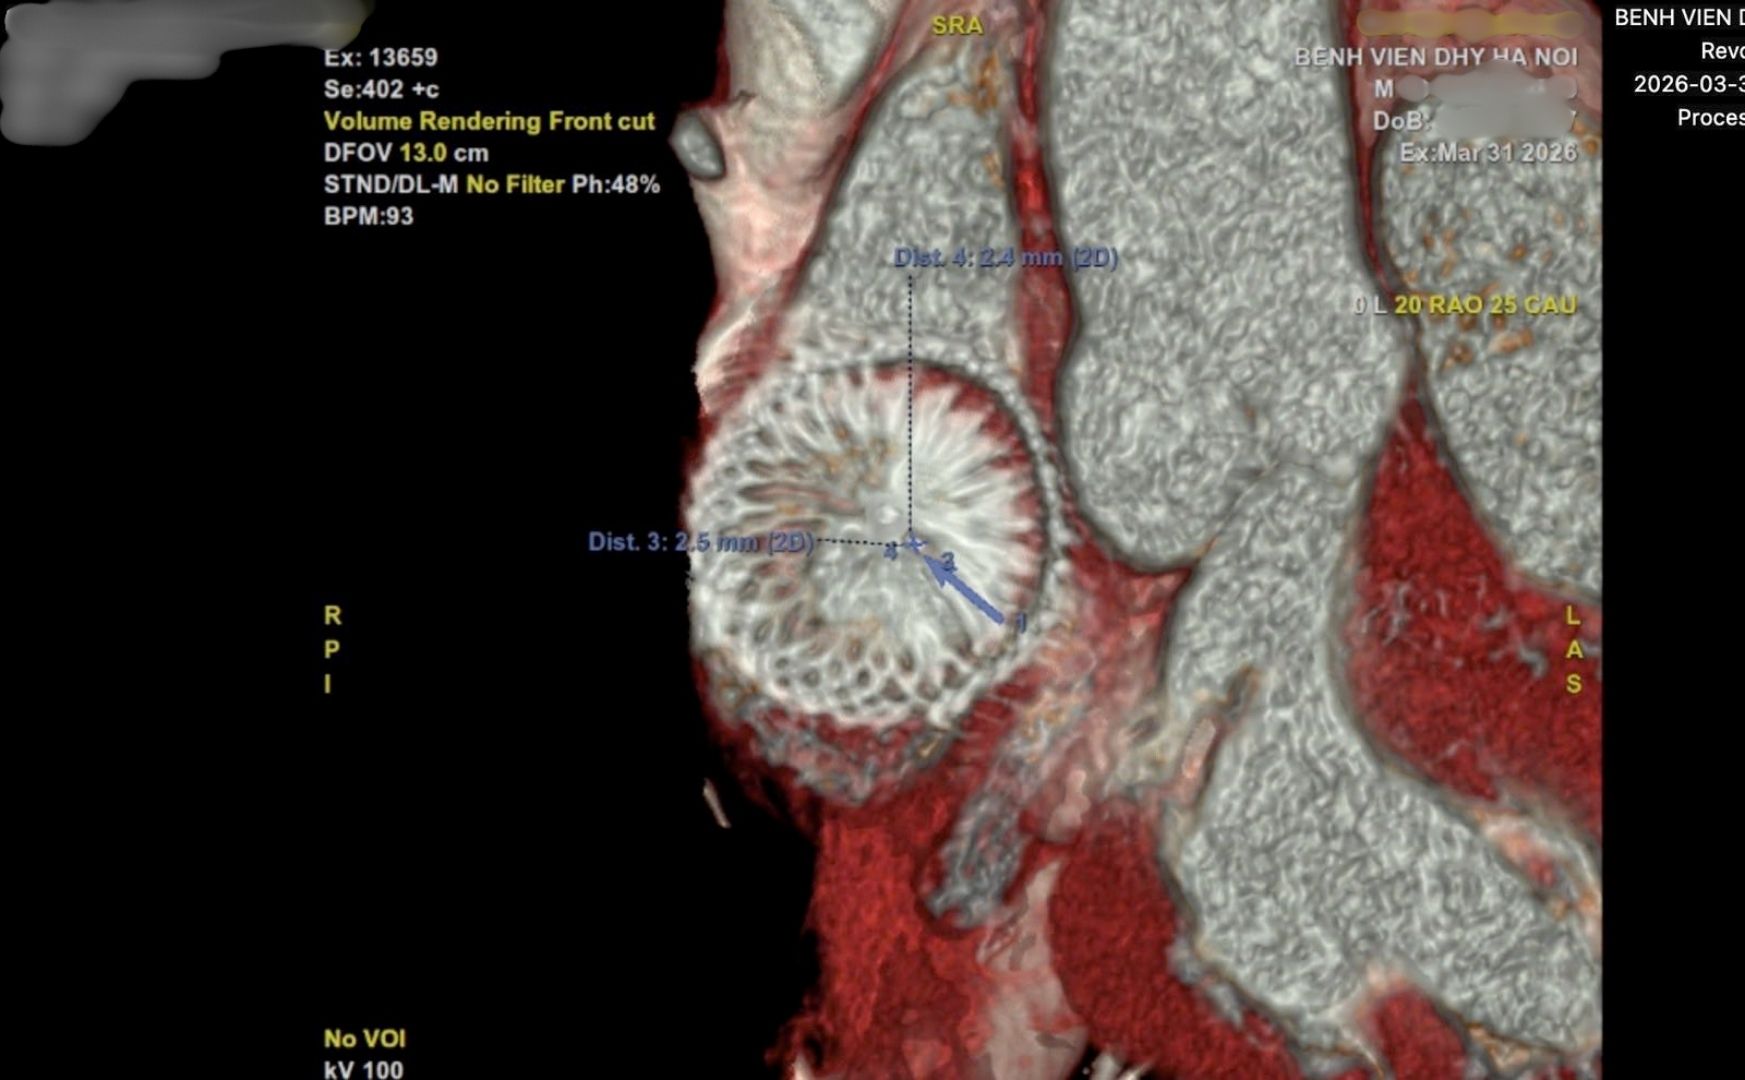

PGS.TS.BS Nguyễn Lân Hiếu - Bệnh viện Đại học Y Hà Nội cho biết, bệnh nhân nam 41 tuổi được phát hiện thông liên nhĩ cách đây 4 năm khi khám vì mệt khi gắng sức. Do phát hiện muộn, lỗ thông rất lớn, gần 4 cm, gây giãn buồng tim và tăng áp động mạch phổi.

Tuy nhiên, đầu năm nay, bệnh nhân tái khám vì cảm giác tim đập nhanh và mệt khi vận động. Kết quả kiểm tra cho thấy xuất hiện dòng máu bất thường từ tim trái sang phải xuyên qua chính dụng cụ đã được đặt trước đó, gây quá tải thể tích và làm tim to trở lại.

Theo PGS.TS.BS Nguyễn Lân Hiếu, việc dụng cụ đã nằm ổn định trong tim suốt 4 năm nhưng lại “thủng” ở giữa là tình huống cực kỳ hiếm. Theo lý thuyết, sau khoảng 6 tháng, dụng cụ sẽ được nội mạc tim bao phủ hoàn toàn, gần như “hòa vào” cấu trúc tim và không thể xảy ra hiện tượng này.